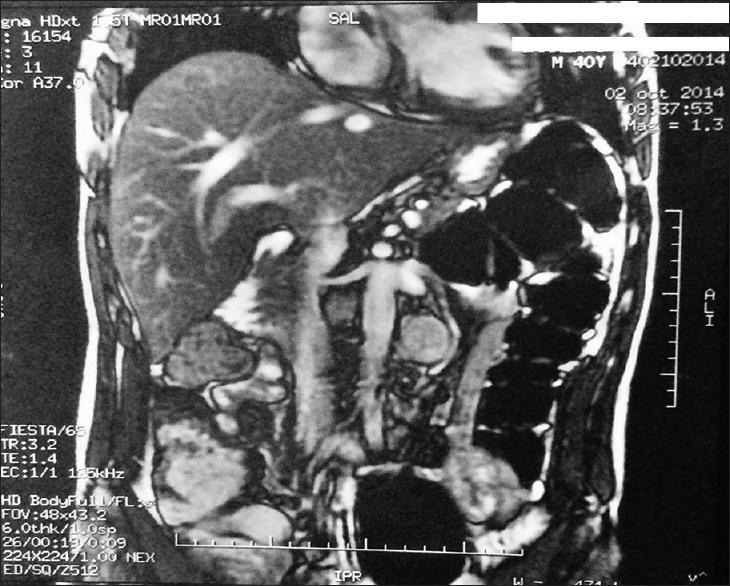

Multiple retroperitoneal paragangliomas.